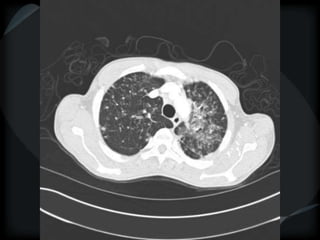

Airspace Patterns

 Perilobular pattern

COP – perilobular pattern